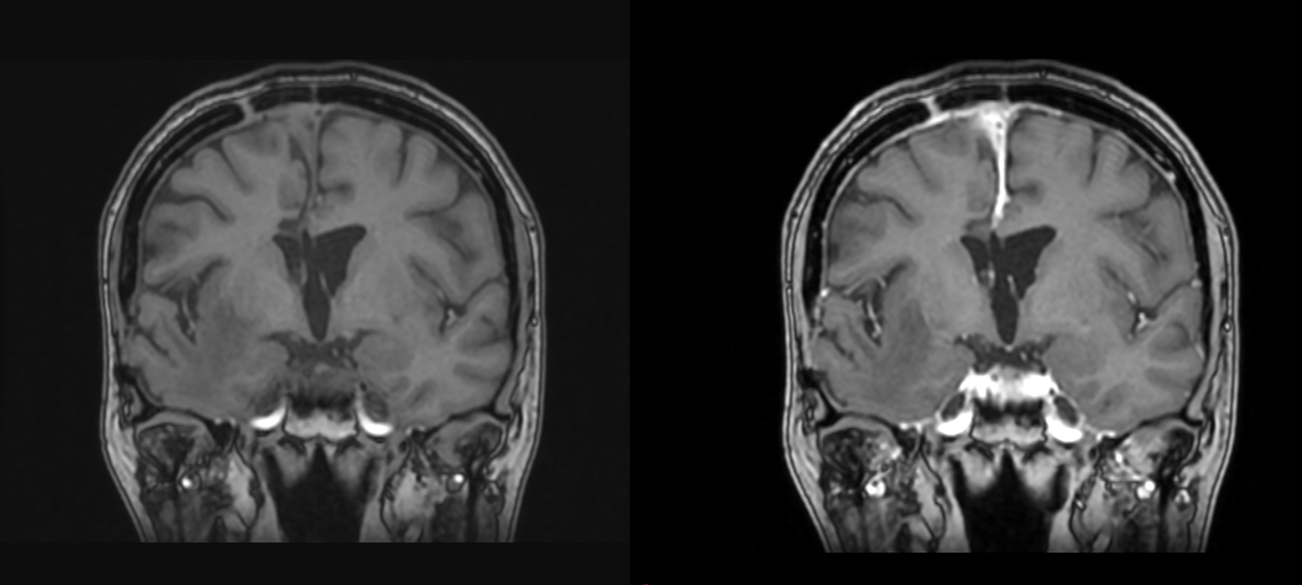

– Investigații imagistice: RMN (rezonanță magnetică) și/sau CT (tomografie computerizată), care evidențiază masa tumorală și hidrocefalia asociată

Datorită poziției profunde (ventriculii laterali sunt situați în mijlocul emisferelor cerebrale iar ventriculul III și IV în mijlocul creierului, înconjurați de structuri vitale), abordul chirurgical al acestor tumori este adesea dificil, reprezentând o provocare chiar și pentru cei mai experimentați chirurgi.